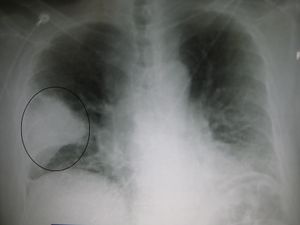

-

Right upper lobe pneumonia as marked by the circle.